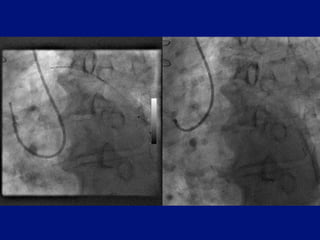

Guide catheter backing out

Backup achieved by contact       As guide backs out –backup

with coronary osteum and aorta   lost as guide comes away from

coronary osteum & aortic wall

JR4

Guide catheter backingout Backup achieved by contact As guide backs out –backup with coronary osteum and aorta lost as guide comes away from coronary osteum & aortic wall JR4